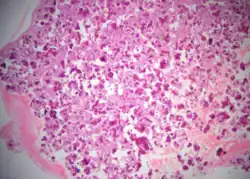

Cemento-ossifying fibroma is a well-demarcated lesion, often encapsulated by a thin fibrous capsule and sharply separated from adjacent normal bone. It shows significant internal variation, with differing amounts of fibrous and mineralized tissue—even within the same lesion. Mineralization is often more prominent centrally and typically includes osteoid, woven to lamellar bone, and dense basophilic cementum-like calcifications. Bony trabeculae may fuse into broad sheets or form thick, anastomosing strands. Osteoblastic rimming is commonly seen around bone trabeculae.[27]

The stroma is fibroblastic and may exhibit areas of hypercellularity and nuclear hyperchromasia; however, mitotic activity is rare and cellular atypia is minimal .[28] The mineralized component may include acellular or paucicellular cementum-like spheres along with bone structures .[28]

Though rare, hemorrhagic cystic degeneration—resembling aneurysmal bone cyst formation—can occur, more commonly in juvenile variants.[27][29] Histological overlap can exist among subtypes: psammomatoid and trabecular JOF may exhibit features resembling COF, and vice versa. In syndromic cases, such as gnathodiaphyseal dysplasia, COF lesions appear more fibrous with basophilic, acellular bone droplets and spherical ossicles, but histologically resemble nonsyndromic counterparts .[30]